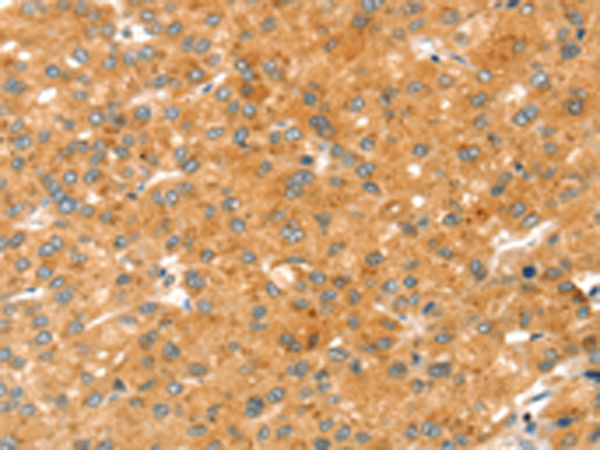

分类: 科研抗体货号: P08683别名: MDT1; CGI82; PSDR1; RALR1; SCALD; ARSDR1; HCBP12; SDR7C1应用: IHC反应种属: Human, Mouse